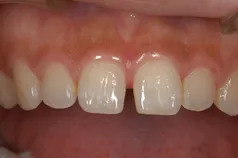

[症例2]

治療前は前歯の間がすいているため、人前で笑えないなどのコンプレックスを持たれていました。

ホワイトニング後、前歯4本をラミネート・ベニアで治療することで引き締まった口元になり、笑顔が多くなりました。

- 治療期間:2ヶ月

- 治療費:45万円

- 治療回数:4回